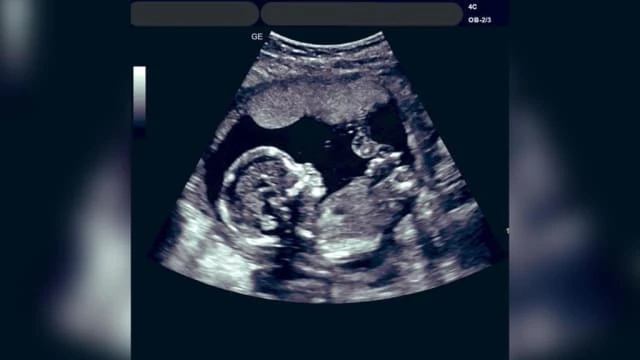

這位阿末醫生說:「這名32歲女性結婚五年了,沒有孩子,最後卻在丈夫不知情的情況下,懷上了其他男人的孩子。」

由於孕婦以及胎兒的健康都沒有問題,這名醫生最終拒絕了女子的墮胎要求,並將她轉介給輔導員,以尋找更好的解決方案。